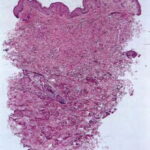

Histopathology. Histologic examination of the involved skin reveals considerable accumulations of swollen and irregularly clumped fibers staining like elastic fibers in the middle and lower thirds of the dermis; that is, they stain deeply black with orcein or Verhoetrs stain . Although normally elastic fibers do not stain with routine stains such as hematoxylin-eosin, the altered elastic fibers in pseudoxanthoma elasticum stain faintly basophilic because of their calcium imbibition. Staining for calcium with the von Kossa method also shows these fibers well. |

In the vicinity of the altered elastic fibers, there may be accumulations of a slightly basophilic mucoid material, which stains strongly positive with the colloidal iron reaction or with Alcian blue . The number of collagen bundles is reduced in such areas, and numerous reticulum fibers are seen on impregnation with silver . In some cases with pronounced elastic tissue calcification, a macrophage and giant cell reaction may be present . |